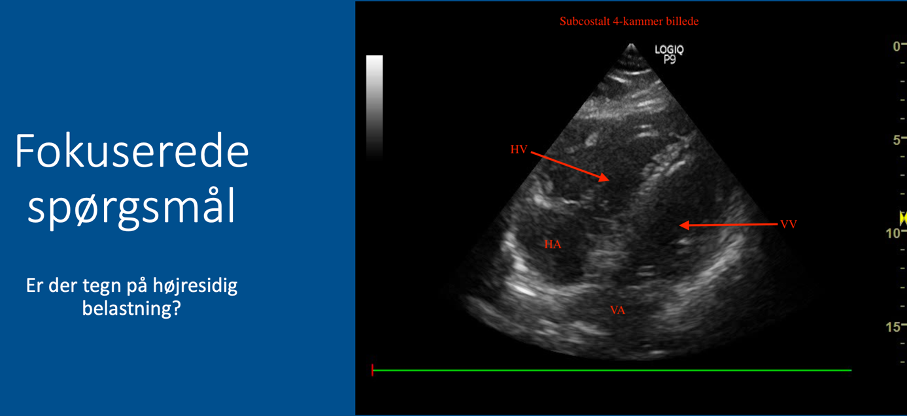

Fokuserede spørgsmål (FHUS):

* Tegn på højresidig belastning: ja/nej?

Vurder størrelsesforhold mellem højre og venstre ventrikel:

* Normalt forhold: VV (2/3) er omtrent dobbelt så stor som HV (1/3) –> INGEN tegn på højresidig belastning

* Abnormt forhold: hvis HV ≈ VV eller HV > VV –> tegn på højresidig belastning